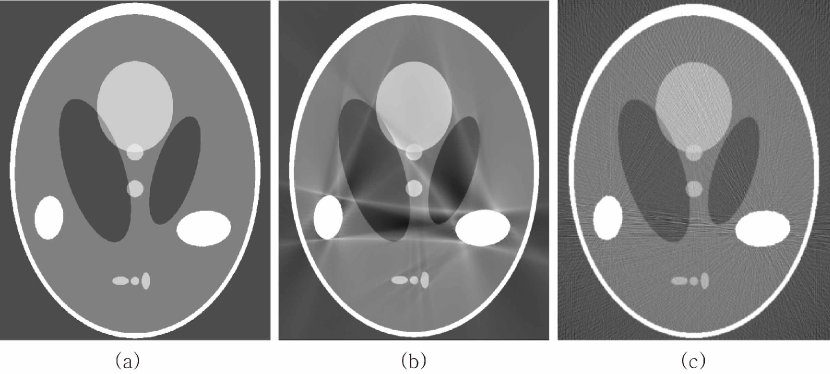

Fig. 3 illustrates how streaking artifacts are produced by the geometric structure of . In Fig. 3, is given by so that contains the line segments and . Using arguments in the proof of Theorem 3.1, we have

Hence, the lines and can be included in . Fig. 3 shows that the lines and are streaking artifacts.

| (36) |

only when if the metal region is not strictly convex. In other words, the streaking artifacts in are related with the geometry of , as shown in Fig. 4. In the figure, we use the Shepp-Logan phantom as and the homogeneous metallic objects with the various geometries are added to illustrate the streaking artifacts in the reconstructed image .